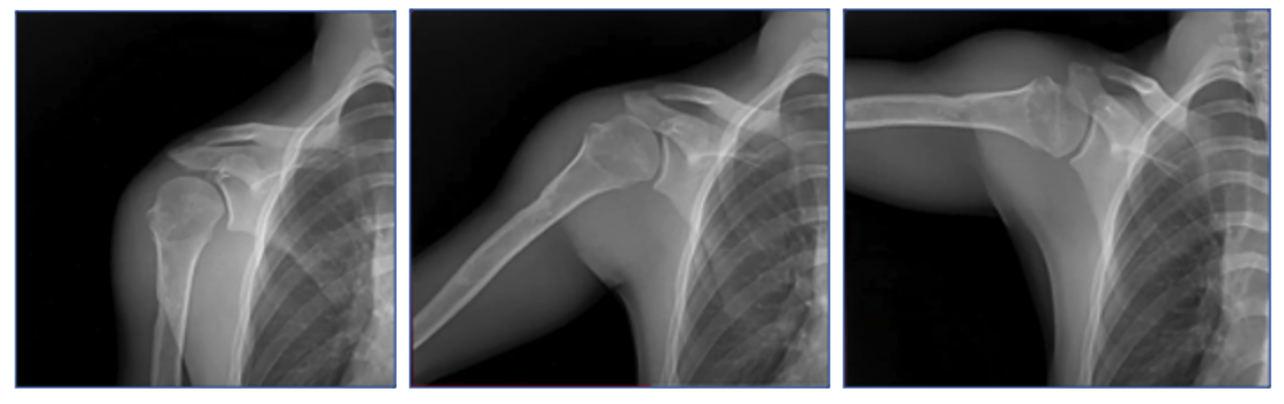

DDR is a radiographic technique that provides a series of individual digital X-ray images acquired at high speed and low radiation dose. These images provide diagnostic-quality views of anatomical structures in motion and the ability to visualize the dynamic interaction with physiological changes over time.

Dynamic Digital Radiography